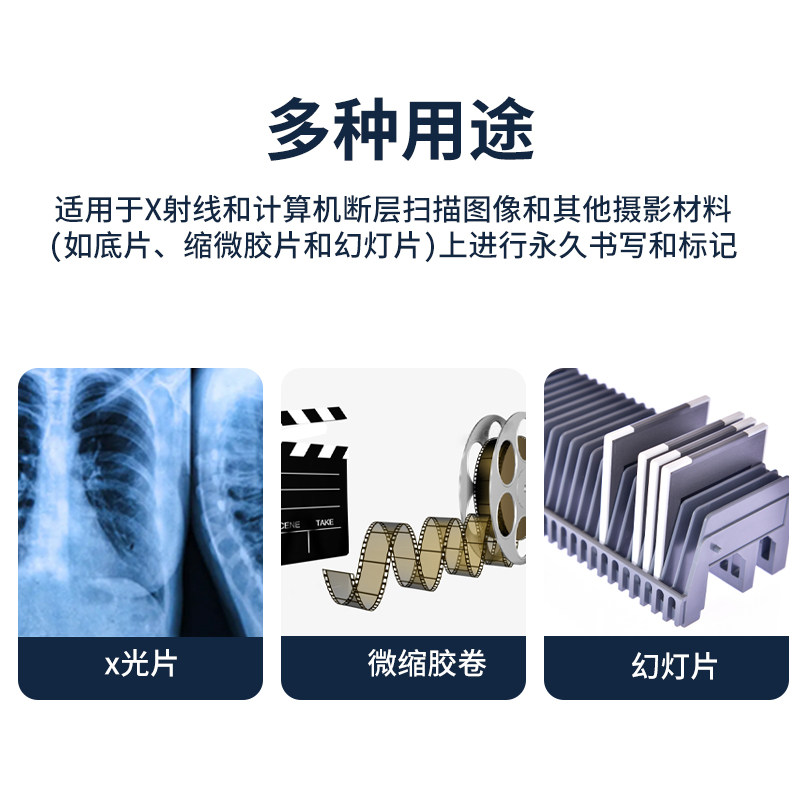

德国Edding 8010 X光片标记笔是一款非常实用的办公和学习工具。它的笔尖细腻,能够在X光片、相机胶卷和幻灯片上清晰书写,干燥迅速,不易晕染。无论是标记文档还是做简单的注释,均能轻松自如,不会影响图像的清晰度。此外,笔的油墨防水且耐光,非常适合长期储存的需要。整体使用体验非常满意,强烈推荐给需要进行标记的用户。

德国Edding 8010 X光片标记笔是一款非常实用的办公和学习工具。它的笔尖细腻,能够在X光片、相机胶卷和幻灯片上清晰书写,干燥迅速,不易晕染。无论是标记文档还是做简单的注释,均能轻松自如,不会影响图像的清晰度。此外,笔的油墨防水且耐光,非常适合长期储存的需要。整体使用体验非常满意,强烈推荐给需要进行标记的用户。